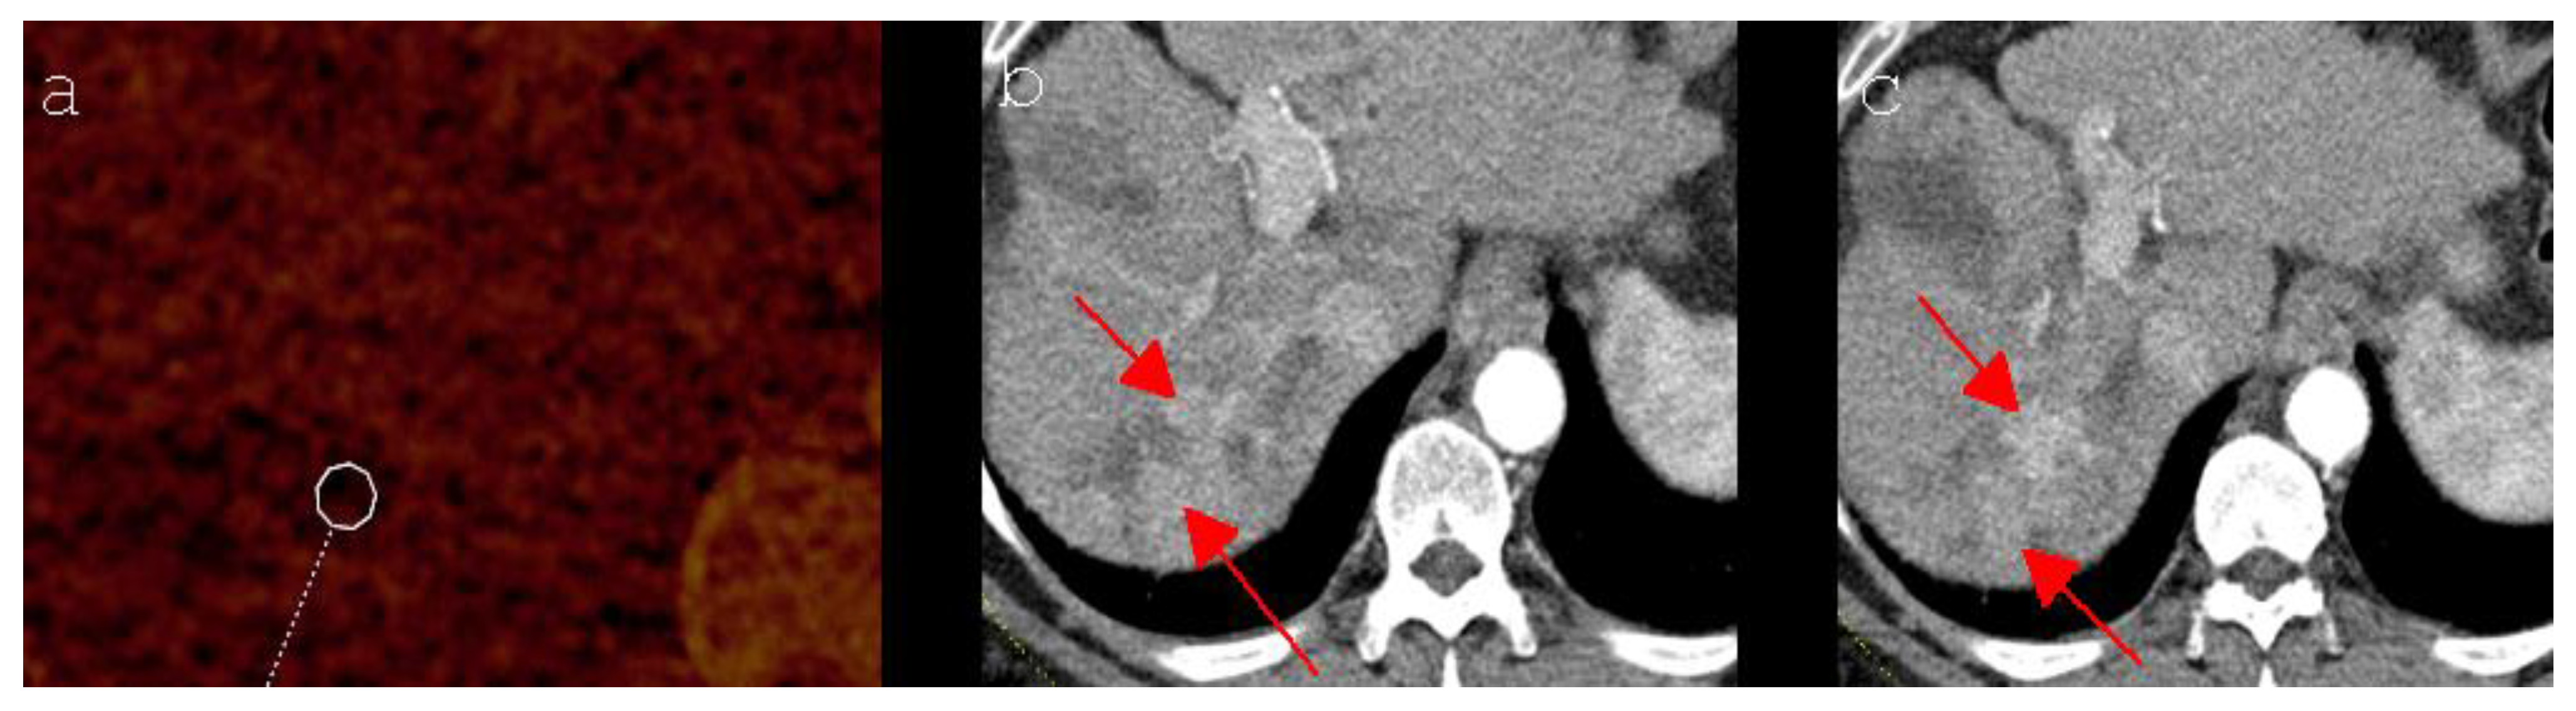

- Bäumler, W.; Wiggermann, P.; Lürken, L.; Dollinger, M.; Stroszczynski, C.; Beyer, L.; Schicho, A. Early detection of local tumor progression after irreversible electroporation (IRE) of a hepatocellular carcinoma using Gd-EOB-DTPA-based MR imaging at 3T. Cancers 2021, 13, 1595. [Google Scholar] [CrossRef] [PubMed]